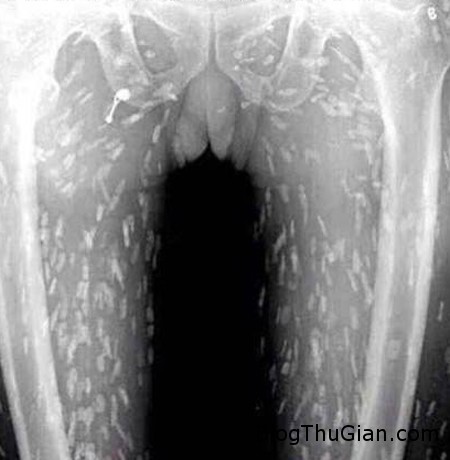

Tuy nhiên, do bệnh tình đã bước sang giai đoạn nghiêm trọng nên người đàn ông tiếp tục được chuyển tới Bệnh viện Nhân dân số 8 ở Quảng Châu để điều trị. Kết quả chụp X-quang cho thấy, những đốm trắng nhỏ xuất hiện lấm chấm khắp cơ thể chính là sán.

Những chấm trắng xuất hiện trên hình chụp X-quang là sán.